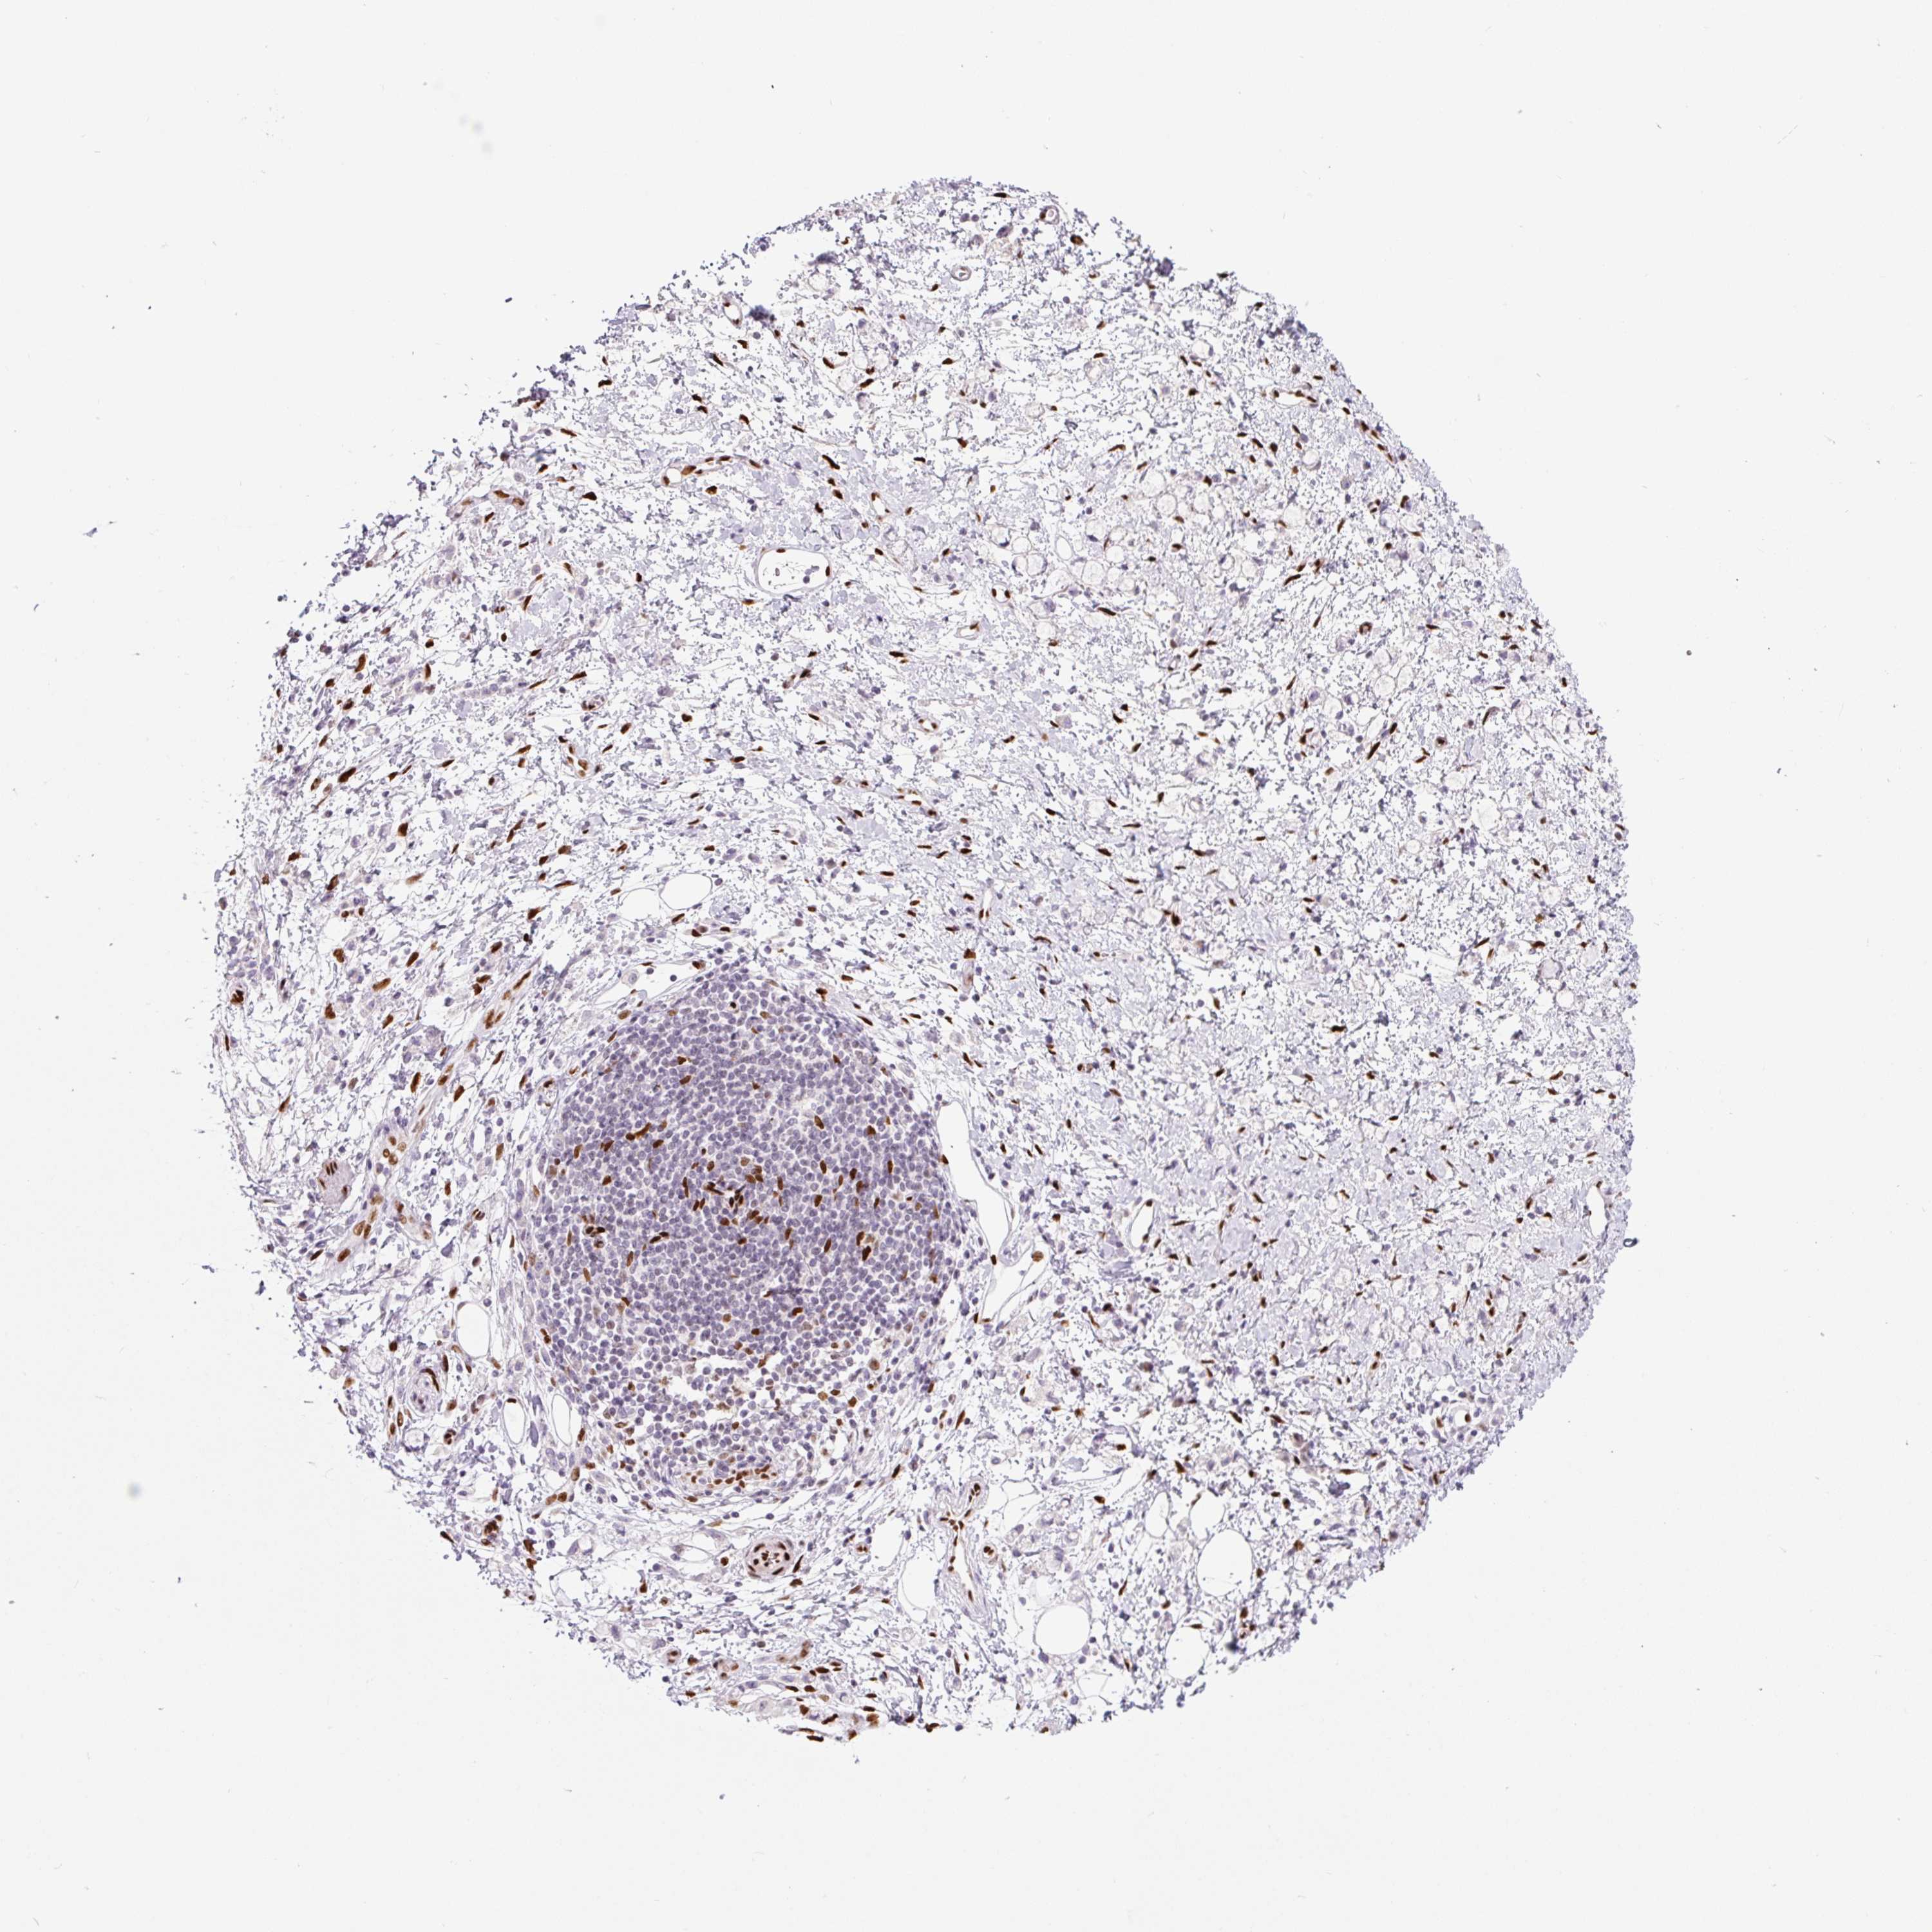

STOMACH CANCER - Protein expressioni

A mouse-over function shows sample information and annotation data. Click on an image to view it in a full screen mode. Samples can be filtered based on level of antibody staining by selecting one or several of the following categories: high, medium, low and not detected. The assay and annotation is described here.

Antibody stainingi

Antibody staining in the annotated cell types in the current human tissue is reported as not detected, low, medium, or high, based on conventional immunohistochemistry profiling in selected tissues. This score is based on the combination of the staining intensity and fraction of stained cells.

Each image is clickable and will lead to virtual microscopy that enables deeper exploration of all samples and also displays staining intensity scores, fraction scores and subcellular localization as well as patient and tissue information for each sample.

Antibody HPA027524

Antibody CAB058686

Antibody CAB079943

Staining

High

Medium

Low

Not detected

Intensity

Strong

Moderate

Weak

Negative

Quantity

>75%

75%-25%

<25%

None

Location

Nuclear

Cytoplasmic/membranous

Cytoplasmic/membranous,nuclear

Adenocarcinoma, NOS

Adenocarcinoma, High grade